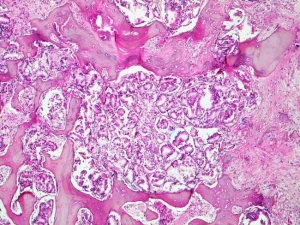

Biyopsi:

Kemik metastazı şüphesi olan hastalarda, kesin tanı koymak için biyopsi yapılabilir. Biyopsi, genellikle metastatik tümörlerin tipini ve kanserin kaynağını belirlemek için önemlidir. Kemik biyopsisi, hastanın kemiklerinden örnek alarak, hücrelerin mikroskop altında incelenmesini sağlar.